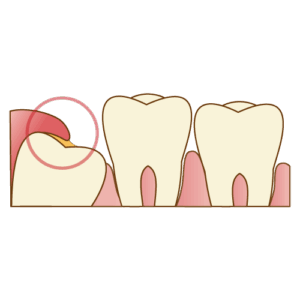

2. 隣の健康な歯(第二大臼歯)がダメになる

これが、私たちが最も避けたいケースです。 親知らずが斜めに生えていると、その手前にある**最も大切な「第二大臼歯(7番)」**の後ろ側に隙間ができ、食べカスが詰まりやすくなります。

結果として、親知らず自身だけでなく、健康だったはずの第二大臼歯が虫歯になったり、歯周病(歯を支える骨が溶ける病気)になってしまうのです。

親知らずは失っても噛み合わせに影響は出にくいですが、第二大臼歯を失うと、噛む機能が著しく低下します。

親知らずを守るために、その手前の重要な歯を犠牲にするわけにはいきません。